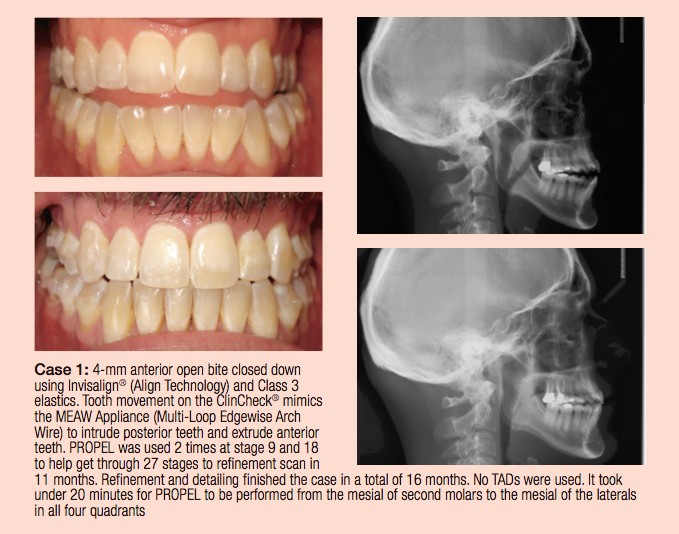

Dr. William Thomas discusses an aligner treatment alternative You have a new prospective patient waiting in your consult room; your treatment coordinator (TC) has provided the patient with the various alternatives to treatment and has informed you that the patient is set on being treated with aligners. The patient records indicate a need for fixed […]